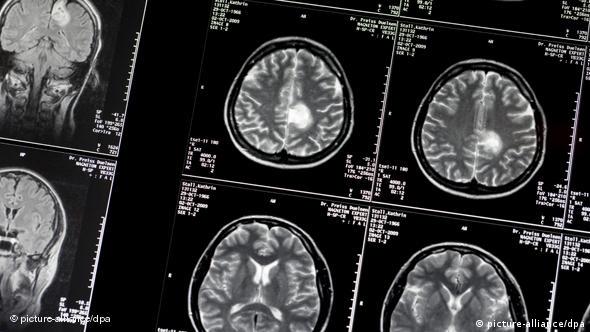

"Θυμάμαι μια περίπτωση ενός νεαρού κομπιουτερά με ένα παιδί τριών μηνών. Απέκτησε πρόβλημα κινητικότητας στα χέρια, μετά στα πόδια, κι έπαθε παραπληγία. Του κάναμε μαγνητική και είδαμε ότι έχει έναν τεράστιο όγκο στο νωτιαίο μυελό σε 7 επίπεδα, στην αυχενική και θωρακική μοίρα. Βάλαμε ένα στοίχημα, ποιος θα περπατήσει πιο γρήγορα, αυτός με τον όγκο ή το παιδί του 3 μηνών; Εγώ είπα ότι θα περπατήσει αυτός πρώτος, και το κέρδισα το στοίχημα. Αυτές είναι οι καλές στιγμές που μας δίνουν δύναμη για να προχωράμε στο επάγγελμά μας, είναι το μεγαλύτερο δώρο. Υπάρχουν βέβαια και οι κακές, που πολύ δύσκολα μπορείς να αποβάλεις από τη μνήμη...".